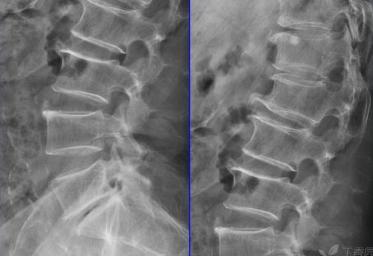

骨赘一般生长在关节面的边缘,为向外凸起的唇样骨性增生,可见于四肢大关节以及脊柱小关节。骨赘和骨刺一样都是由损伤引起自我修复的结果。

由于退变、关节不稳、韧带松弛及剧烈活动等原因,可以引起关节面边缘之间挤压摩擦损伤,引起骨膜下出血、水肿及炎症,骨膜细胞和间充质细胞在细胞因子的作用下分化成成骨细胞,继而在关节面边缘不断形成不规则的骨质,也就是骨赘,骨赘在一定意义上起到为关节提供代偿稳定的作用。

但是,如果增生严重,影响到关节的稳定性、形态、功能,或者卡压神经引起神经症状,则需要手术治疗。